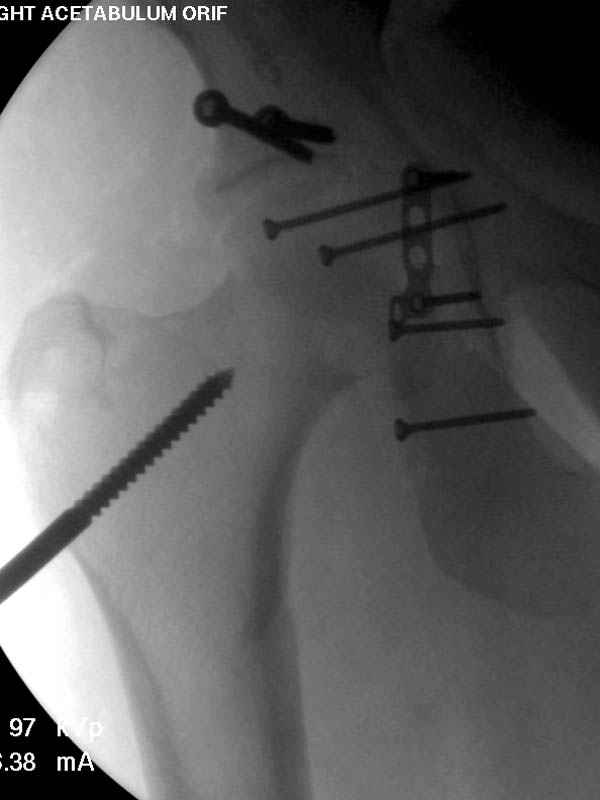

Дополнительно имеется перелом ацетабулума: задняя

колонна с полупоперечным переломом, и переломы костей лица.

На седьмой день зафиксирован перелом ацетабулума через задний доступ. Перед операцией для профилактики DVT, IVC фильтер, также получает Lovenox.

По снимку создается впечатление о высоком поперечном переломе, задней колонны, стенки; почему не пользовались *magic screw*?

Не хотелось отклонятся от основной темы, поэтому здесь краткие ответы..

Латеральное положение облегчает проведение тракции через вертел, за 5 мм стержень за вертел (грузом через тракционное приспособление), на обычном рентгенопрозрачном операционном столе, а для положения на животе, наверное, Judet Table более приемлем, потому что там имеется латеральное тракционное устроиство.

Там множество обычных 2.7 мм шурупов, потом идет фиксация основными пластинами.

Снимки здесь....